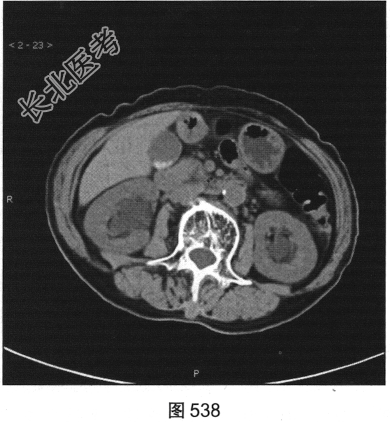

- 多项选择题3.[提示]CT平扫+增强(图538~图542)所见:双侧肾盂肾盏旁可见沿肾盂肾盏走行的多发囊样低密度灶, 未见明显强化。应考虑的鉴别诊断为( )

A、肾外肾盂旁血管病变

B、肾盂旁肿瘤性病变

C、囊性肾癌

D、肾盂旁囊肿

E、肾积水

F、肾窦内脂肪沉积症